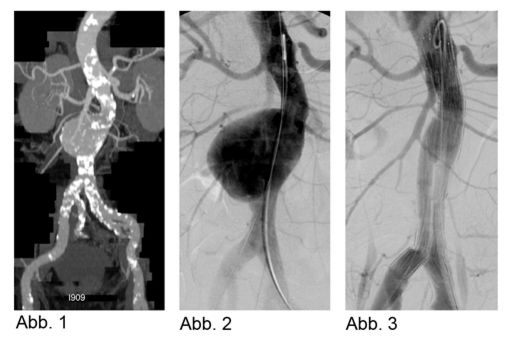

Die Abdomensonographie ist als Screeninguntersuchung und für eine routinemäßige Verlaufskontrolle bei Aneurysmen gut geeignet. Zur exakten Bestimmung der Größe und Morphologie wird jedoch eine Computertomographie (Abb. 1), in Ausnahmefällen eine Magnetresonanztomographie, durchgeführt.

Alternativ zur offenen chirurgischen Therapie eines Aortenaneurysmas besteht die Möglichkeit einer endovaskulären Aneurysmaausschaltung mittels eines Stentgrafts (gewebeummanteltes Metallgittergeflecht). Voraussetzung für die endovaskuläre Therapie ist jedoch eine anatomische Eignung, welche eine ausreichende Weite der Beckengefäße und nötige Verankerungszonen für den Stentgraft mit sich bringt. Die Stentgraft Implantation wird von Interventionellen Radiologen in Zusammenarbeit mit Anästhesist:innen und Gefäßchirurg:innen durchgeführt. Der Eingriff erfolgt unter Spinalanästhesie oder einer Allgemeinnarkose. Der Zugang zum Aneurysma wird üblicherweise durch einen kurzen Schnitt in der Leiste geschaffen. Zur Darstellung des Aneurysmas wird zuerst eine Angiographie der Bauchaorta durchgeführt (Abb.2). Folglich wird unter Röntgendurchleuchtung der Stentgraft über einen Führungsdraht in die Bauchaorta eingebracht und unterhalb der Nierenarterien verankert. Eine Kontrollangiographie nach Stentgraft-Implantation wird zum Nachweis eines guten Ausschlusses des Aneurysmas durchgeführt (Abb.3).

Bei elektiver chirurgischer Sanierung von Descendensaneurysmen wird die 30-Tages-Mortalität mit 5–13% angegeben. Weitere postoperative Komplikationen sind respiratorische Probleme, bis zu 33% neurologische Defizite und renale Insuffizienz bis zu 8%. Die endovaskuläre Stentgraft-Therapie hat deutlich geringere Mortalitäts- und Komplikationsraten und hat als Alternativmethode eine große Bedeutung in der Behandlung von Aneurysmen in der Aorta descendens und des Aortenbogens erlangt. Bei Beteiligung des Aortenbogens sind vorausgehende chirurgische Umbauten von Aortenbogenästen erforderlich, um eine Stentgraft Verankerung zu ermöglichen. Abbildung 4a zeigt ein Aneurysma mit Beteiligung des Aortenbogens und Abgang der linken Halsschlagader (Arteria carotis) und der linken armversorgenden Arterie (Arteria subclavia) in Nahebeziehung zum Aneurysma. Eine Stentgraft-Therapie kann in solchen Fällen nach Verlagerung (Transposition) der Arteria carotis und Arteria subclavia durchgeführt werden (Abb. 4). Die CT-Kontrolle bestätigt die korrekte Lage des Stent-grafts und den Ausschluss des Aneurysmas.